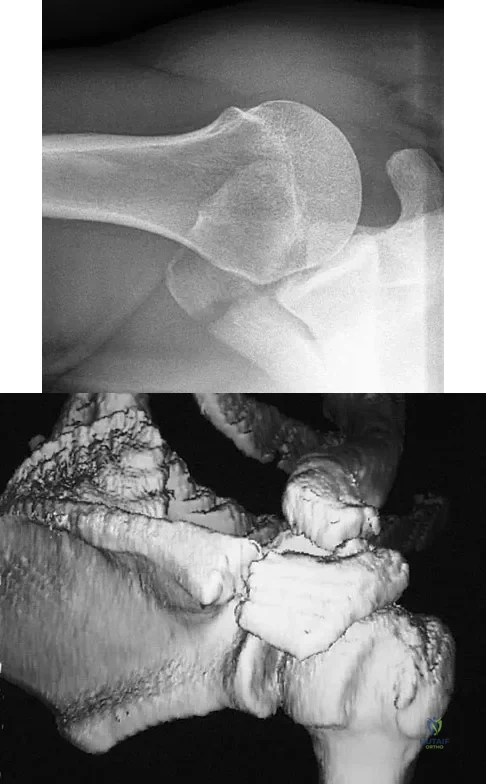

A 51-year-old male truck driver has had progressive left hip pain for more than 2 years, and he reports that the pain has become severe in the past 9 months. He is now unable to work because of the pain. Examination reveals that range of motion of the hip is limited to 95 degrees of flexion, 0 degrees of internal rotation, and 20 degrees of external rotation. The plain radiograph, MRI scan, and intraoperative gross photographs are shown in Figures 9a through 9d. Management should consist of